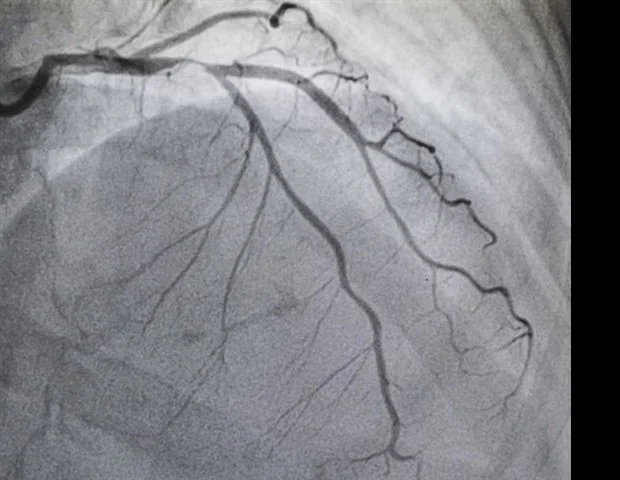

All fifty procedures concluded successfully, yielding a 100% technical and clinical success rate across both the robot-assisted and manual intervention groups. The visualization of all targeted vessels was clear and met the requisite diagnostic standards.